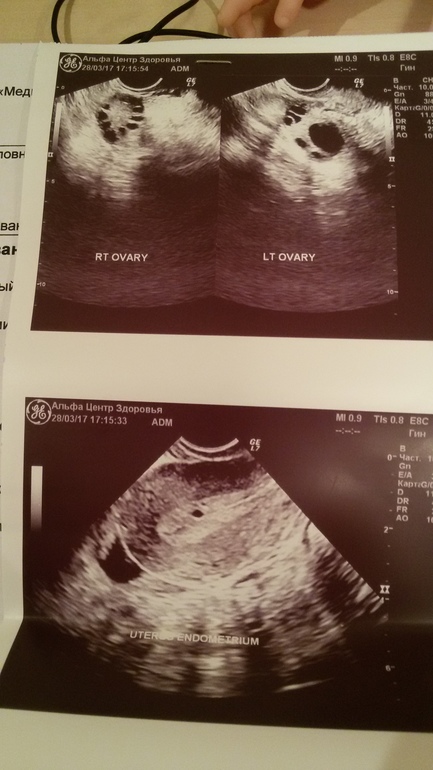

Узи на 10 дц

Мне что интересно - в заключении Признаки перенесённого эндометрита, это как это он у меня перенесся незаметно, так может быть? Дело в том, что прошёл 3 цикл после чистки ЗБ,в первый цикл я делала узи, во второй мерила бт - всё ок

Другой вопрос) ДФ 17×18 - это ведь до овуляции пару дней? У меня НИКОГДА не было такой ранней О - на 18-19 дц стабильно

А вообще меня бы смутило неоднородность эндометрия, кистозные включения... Я бы обратила внимание.ну и мультифолликулярные яичники тоже не айс. В общем надо бы все это в порядок привести.